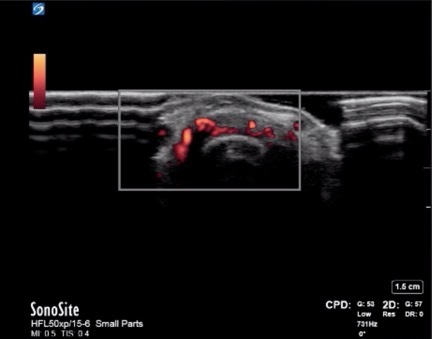

Hand MCP Joint Synovitis Early RA Seronegative Transverse Image